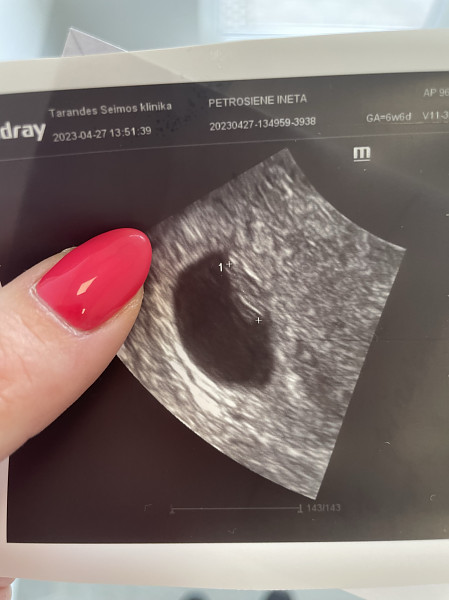

Ramzio vaisiaus lyties nustatymo teorija

Pagal Ramzio teoriją kūdikio lytį galima nustatyti labai anksti, 6-8 nėštumo savaitę iš pradėjusios formuotis placentos vietos. Skaityti visą straipsnį